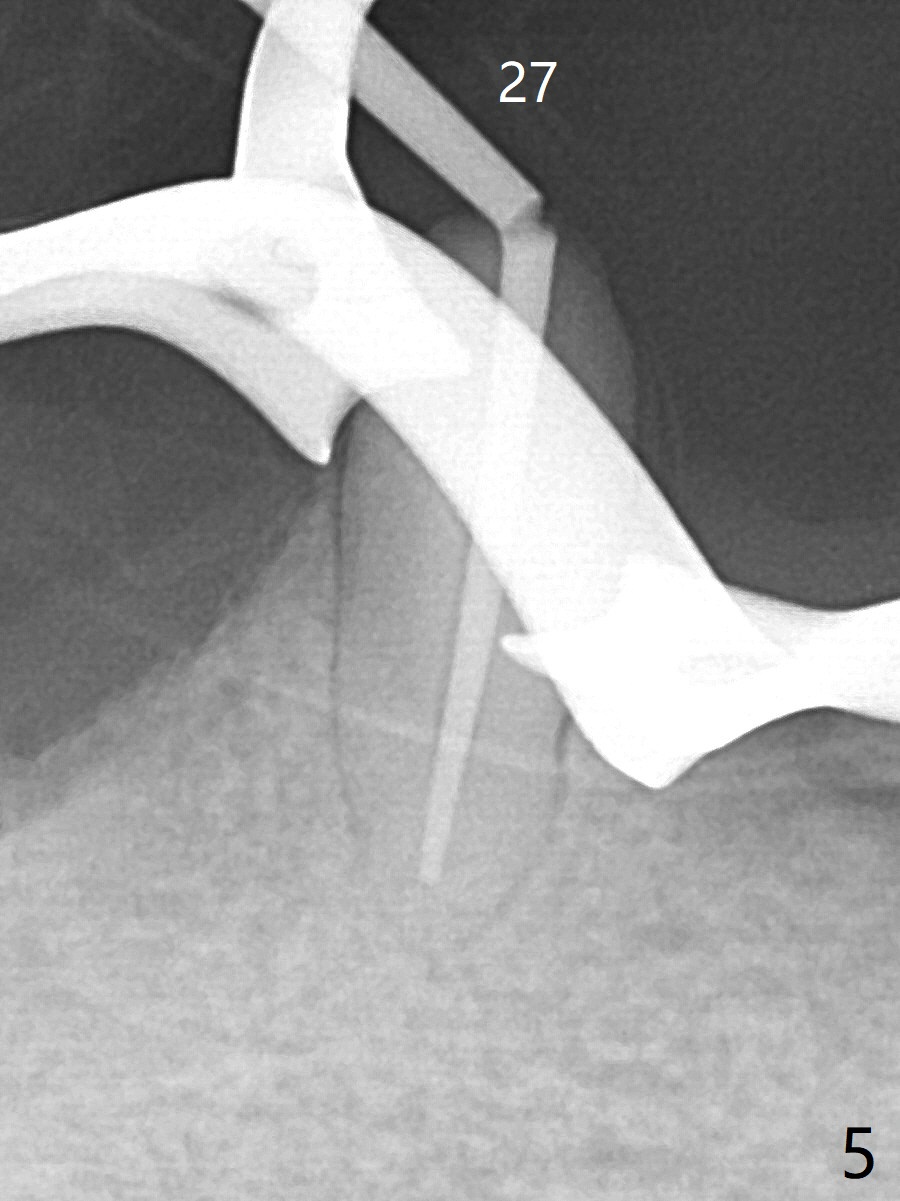

60岁男两年前回国制作下颌活动假牙,之后没有什么护理,五个基牙四个坏的厉害(图一(上面):21,22,27,31),初步计划:21,22,27号牙根管治疗(图二,三),31号牙拔除种植(申请保险,图四),都装上球状基台(ball abutment),增加托牙稳定性。当牙根基牙不行时,再逐步改做植牙。深洗和14号牙(图一)拔出后十四天病人回来进行27号牙(右下3)根管治疗(图五,六),工作长度13毫米,合适打桩做牙冠吗(原有局部托牙有卡环(Clasp and rest)?还是安置球冒更恰当?